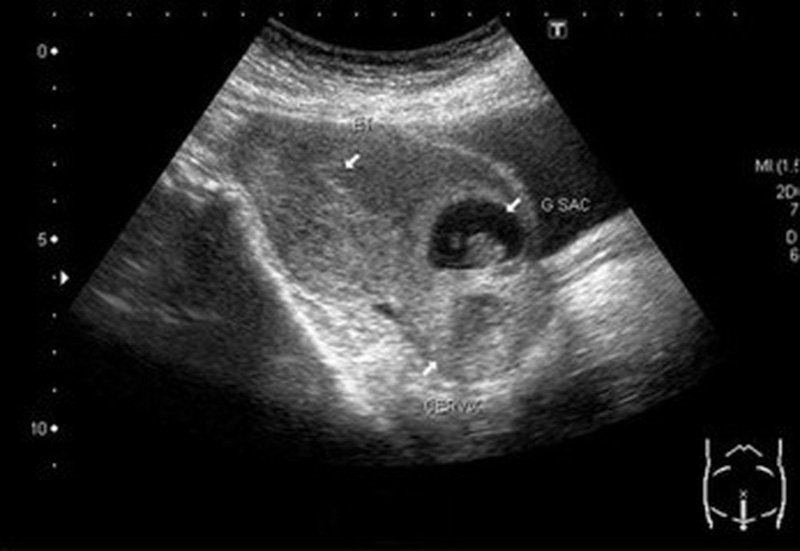

Chửa tại vết mổ đẻ cũ là gì?

Chửa tại vết mổ đẻ cũ là quá trình mang thai và sinh con thông qua vết mổ đã được thực hiện trước đó. Theo các chuyên gia y tế, phương pháp này không nên được lựa chọn nếu không cần thiết, vì nó có thể gây ra nhiều nguy hiểm cho cả mẹ và em bé.